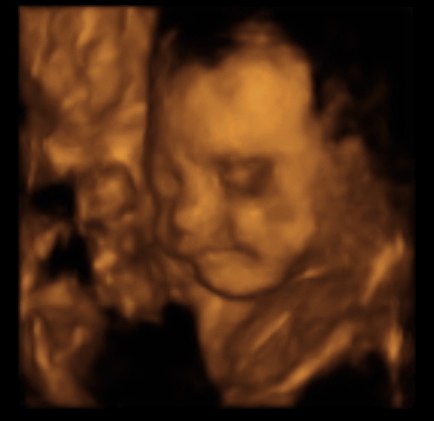

Har været til 3D scanning, hvilket var en fantastisk oplevelse...

Synes lige jeg ville dele nogle af billederne med jer....Så her har i lille Madicken

Hvor ser ud dog fin ud!!!!